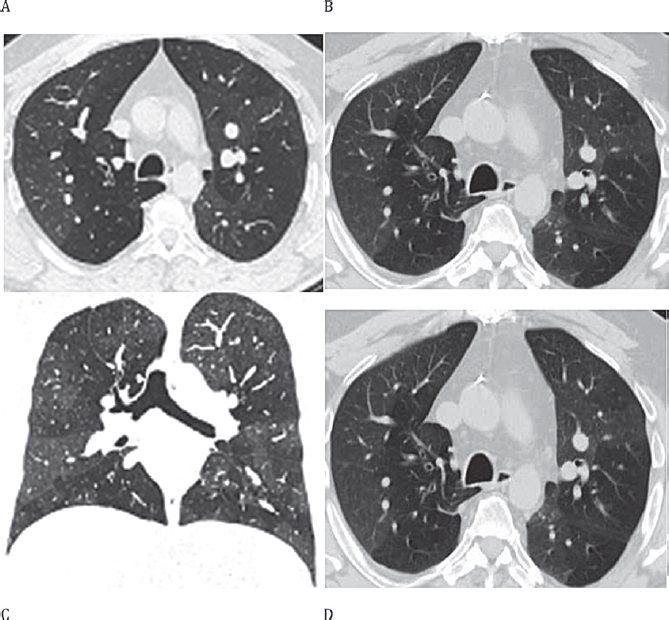

All’HRCT (High-resolution CT) si documentò un franco aspetto a mosaico con aree di iperdiafania distribuita a chiazze, con vasi ridotti in numero e calibro (oligoemia). Alle scansioni in massimo espirio, inoltre, il pattern a mosaico si accentuava, configurando ampie e caratteristiche aree di air trapping espiratorio.

L’esame videofibrobroncoscopico con BAL mise in luce una modesta alveolite neutrofila (NEU 11%). All’ecocardiografia fu evidenziato un impegno notevole a carico delle sezioni destre, con globale aumento delle dimensioni cavitarie: dilatazione del ventricolo destro (DTD 48 mm), dell’atrio destro e dell’arteria polmonare; ballooning del setto interatriale; pattern transmitralico da alterato rilasciamento; PAPs = 40 mmHg. L’angio TC confermò l’assenza di difetti di riempimento (escludendo l’ipotesi tromboembolica), l’aumento delle dimensioni del tronco polmonare (35 mm) e dei rami principali (dx 29 mm, sx 22 mm). Il paziente quindi fu sottoposto a cateterismo cardiaco destro. L’esame svelò un difetto congenito di anomalo ritorno venoso di entrambe le vene polmonari destre in atrio destro (reperto non evidenziato all’angio-TC eseguita precedentemente), cui conseguiva ipertensione polmonare da iperafflusso. Le resistenze polmonari erano normali e la coronarografia associata non documentò lesioni significative delle coronarie epicardiche. Fu programmato l’intervento cardiochirurgico, che permise la correzione con successo del difetto con ridirezione delle vene polmonari destre superiore ed inferiore nell’atrio sinistro. Il paziente fu successivamente monitorato in équipe presso la Cardiologia e la Pneumologia del nostro Ospedale, con controlli ecocardiografici seriati post-intervento, che evidenziarono una rapida normalizzazione della PAP sistolica ed una progressiva riduzione di volume del ventricolo e dell’atrio destro. Al contrario, gli esami di funzionalità respiratoria ad 1, 2, e 3 anni e le immagini HRCT non mostrarono alcuna restitutio delle alterazioni precedentemente osservate (Figura 1), nonostante il regime terapeutico instaurato con corticosteroidi inalatori e sistemici e broncodilatatori long-acting. Sulla scorta dell’anamnesi, dei dati funzionali e del reperto HRCT, fu posta diagnosi di bronchiolite costrittiva criptogenetica.

Figura 1.HRCT pre- e post- intervento. A) TC inspiratoria pre-intervento. B) TC espiratoria pre-intervento. C) Ricostruzione multiplanare piano coronale pre-intervento. D) TC espiratoria post-intervento.